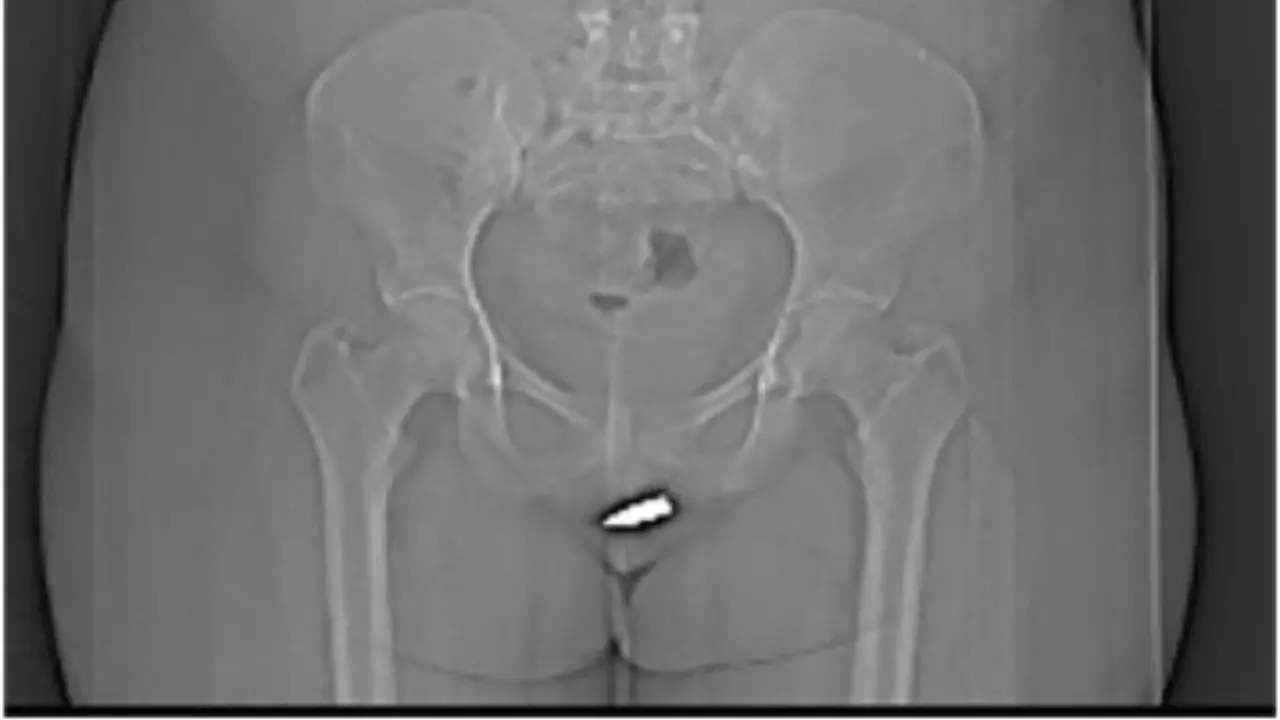

2 cm de long et 0,8 cm de diamètre. Voici les dimensions de la balle perdue qu’a reçu une jeune femme de 24 ans alors qu’elle était simplement en tain de se reposer dans son salon. Un fait divers qui pourrait paraître assez fréquent dans un pays en guerre comme la Somalie. Mais il s’agit en réalité d’une première dans la littérature scientifique.

Prise en charge en urgence dans un hôpital de Mogadiscio, la capitale somalienne, la patiente âgée de 24 ans a indiqué qu’elle se trouvait dans son salon lorsqu’une balle est venue traverser son plafond avant de finir sa course dans son clitoris. Heureusement pour elle, le projectile avait perdu en vitesse et en puissance après le coup de feu.

La patiente a donc été placée sous anesthésie locale, avant que l’équipe médicale ne procède à l’opération : une simple incision à hauteur de la vulve, pour retirer la balle de 2 cm de long.